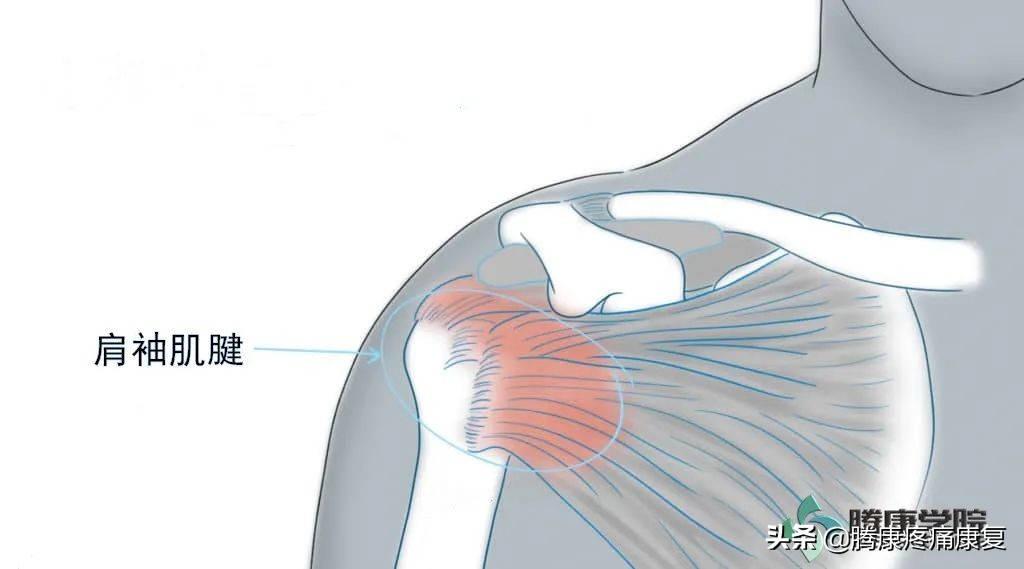

急性肩关节病变可能与肩袖肌腱钙化相关。在出现疼痛以前,钙化可能已存在数年而没有症状,伴有钙质吸收。这一过程可能影响肩关节活动度和生活质量,但是其自然病程往往会自然恢复。钙化性肌腱炎可能较少见于手部、前臂和下肢的其他肌腱。

- 在 钙化后期 过程中出现肩袖愈合和修复。某些患者疼痛可能持续数月,影响功能。钙化最常累及冈上肌肌腱,随后是冈下肌肌腱,小圆肌肌腱和肩胛下肌肌腱。

- 受累肩袖肌腱压痛。